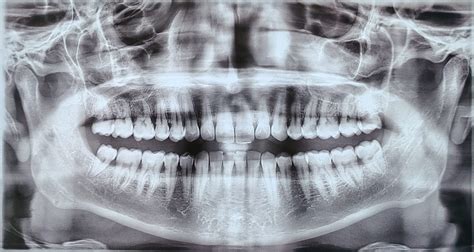

Enfermedad periodontal

Sin duda, la enfermedad periodontal es la causa número uno de movilidad y pérdida de dientes en adultos. Todo suele comenzar con unas encías inflamadas y sangrantes (gingivitis) que no se tratan a tiempo.

La placa bacteriana y el sarro acumulado bajo la encía van destruyendo progresivamente el ligamento periodontal y el hueso alveolar que rodea al diente. Durante bastante tiempo no duele, por eso es “silenciosa”. Meses o años después, cuando ya hay daño avanzado, es cuando ¡zas!

Encías que sangran al cepillarte, retracción (dientes que se ven más “largos”), mal sabor de boca, dientes que cambian de posición o se espacian… Todos estos son síntomas de alarma.

De hecho, la movilidad dental es un signo tardío de periodontitis - cuando aparece, significa que una parte importante del soporte del diente ya se ha perdido.

La Sociedad Española de Periodoncia (SEPA) advierte que las enfermedades de las encías, si no se tratan adecuadamente, provocan pérdida ósea y movilidad progresiva, hasta la caída de los dientes.

La buena noticia es que, detectada a tiempo, la periodontitis tiene tratamiento y podemos frenar su avance. Pero hay que actuar antes de que la movilidad sea irreversible.